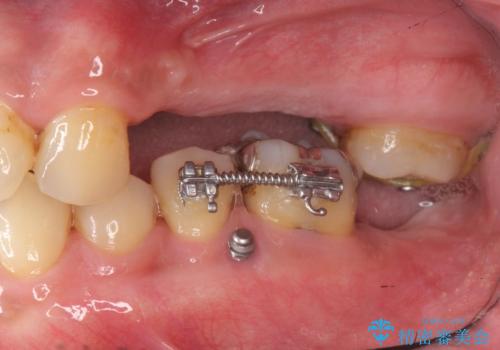

・対合歯の欠損による歯の挺出→マイクロインプラントを用いた小矯正を行うことで咬合平面を是正

噛み合う歯が欠損し長時間放置すると、歯が挺出(歯が伸びてくる)し欠損補綴を行おうにもスペースが足りない場合があります。(クリアランスの不足)

加えて咬合平面の乱れを放置したまま無理やり補綴治療を行うと、特定の部位に過大な力がかかり当該歯を痛めてしまうこともよくあります。

今回、左下6は頬側歯頚部に虫歯があり圧下を行ったことからクラウンにより補綴を行いました。